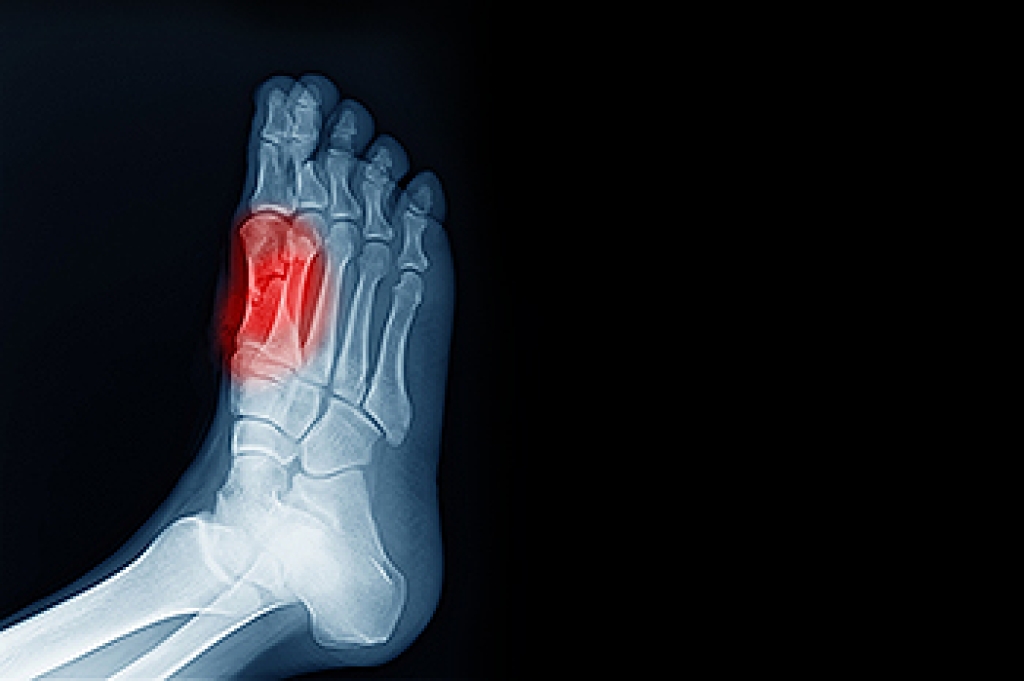

Poor circulation can be common among older people. It is a condition that can affect the feet, and pain and discomfort may ensue. When circulation is good, existing wounds and cuts can heal quickly, and the body may be able to successfully ward off other ailments. Poor circulation is defined as a lack of oxygen that is needed by vital organs. Symptoms of poor circulation are often found in the feet and can consist of a tingling or numbing sensation. The feet may also be swollen, and the skin may become dry. Poor circulation can be caused by diabetes and atherosclerosis. This is a condition that causes a buildup of plaque in the arteries, and they can become narrow, possibly lessening blood flow. There can be additional health conditions that can lead to getting poor circulation, including smoking, consuming excess alcohol, and being overweight. Mild relief may be found when compression stockings are worn, and a gentle exercise routine is frequently performed. If you have poor circulation, it is suggested that you confer with a podiatrist who can offer you relief and treatment options.

Peripheral artery disease (PAD) can potentially lead to poor circulation in the lower extremities. PAD is a condition that causes the blood vessels and arteries to narrow. In a linked condition called atherosclerosis, the arteries stiffen up due to a buildup of plaque in the arteries and blood vessels. These two conditions can cause a decrease in the amount of blood that flows to your extremities, therefore resulting in pain.